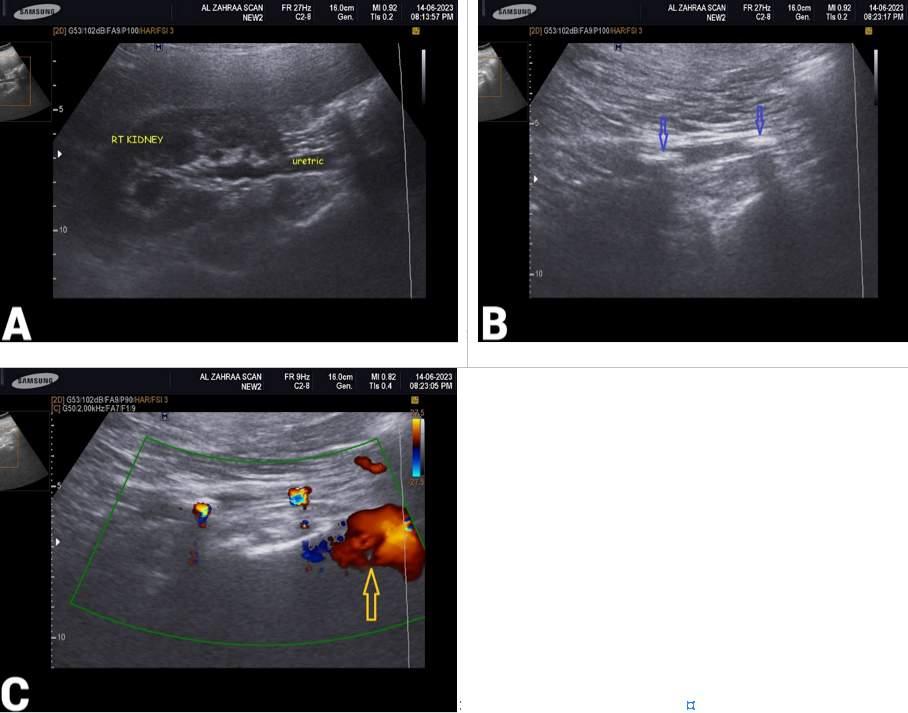

Issuu converts static files into: digital portfolios, online yearbooks, online catalogs, digital photo albums and more. Sign up and create your flipbook.